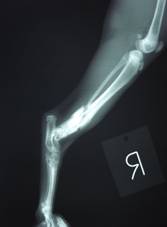

冷蔵庫の上から落下し右後肢を骨折した。

レントゲン写真にて、下腿骨遠位の骨折が認められる。

幸いにも骨折部位の大きな変移は無いようである。

骨折部の内出血をみとめる。

今回はキプス固定による治療を選択する。